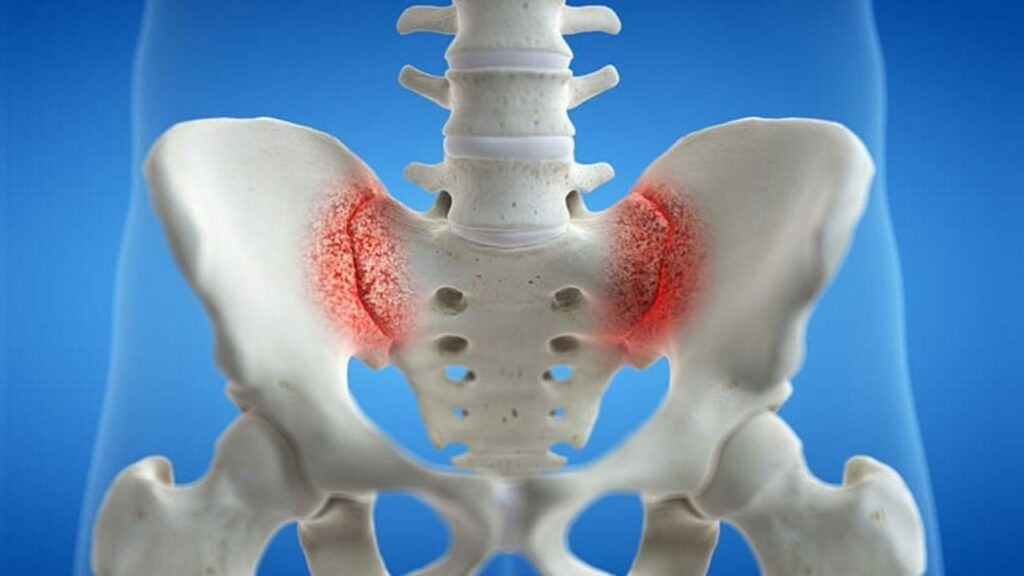

A dor na região lombar baixa ou nas nádegas é uma das queixas mais comuns nos consultórios de ortopedia. Embora frequentemente associada a hérnias de disco ou problemas musculares, muitas vezes a origem da dor está na articulação sacroilíaca. A sacroileíte, que é a inflamação desta articulação, compromete a estrutura que conecta a base da coluna (sacro) à bacia (ilíaco), sendo essencial para a absorção de impacto entre o tronco e os membros inferiores.

Diagnóstico preciso O diagnóstico é feito pela combinação do exame clínico, com manobras específicas que provocam a dor na articulação sacroilíaca, e exames de imagem. Radiografias podem mostrar sinais de artrose ou inflamação crônica, mas a ressonância magnética é o exame mais sensível para detectar a inflamação (edema ósseo) precocemente e avaliar as estruturas adjacentes em detalhe.